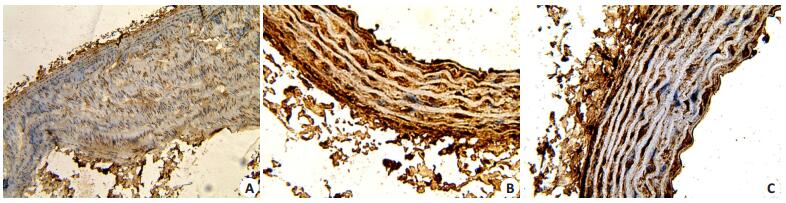

2.1 病理形态学改变光镜下对照组主动脉组织内膜、中膜、外膜3层结构完整,层次分界清楚,内膜层薄、未见斑块;干预组内膜层局部有斑块形成、泡沫细胞较少,内膜增生程度较轻,弹力纤维和胶原纤维排列较对照组紊乱。实验组内膜层结构较前两组明显增厚,脂质斑块浸润,并见有较多泡沫细胞聚集,平滑肌细胞、弹力纤维和胶原纤维排列较紊乱,中膜弹力纤维也较对照组和干预组增粗(图 1)。

图 1 血管组织HE染色结果 Figure 1 HE staining of the aortic tissue in different groups. A: Control group; B: Experimental group; C: Intervention group (HE staining, original magnification: ×100). |

在本研究中光镜下对照组主动脉组织内膜、中膜、外膜3层结构完整,层次分界清楚,内膜层薄、未见斑块;干预组内膜层局部有斑块形成、泡沫细胞较少,内膜增生程度较轻,弹力纤维和胶原纤维排列较对照组紊乱。实验组内膜层结构较前两组明显增厚,脂质斑块浸润,并见有较多泡沫细胞聚集,平滑肌细胞、弹力纤维和胶原纤维排列较紊乱,中膜层胶原纤维和弹力纤维也较对照组和干预组增粗。